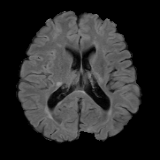

We obtain a subject-wise mean Dice score of 32.94% without any post-processing. By using a simple post-processing with erosion and dilation with filters, this number improves to 48.20% mean Dice score. In comparison, a similar study conducted by [3] consisting of a multitude of algorithms including AnoVAEGAN [4] and f-AnoGANS, obtained a best mean score of 27.8% Dice after post-processing by f-AnoGANS. Before post-processing the best method was Constrained AutoEncoder [8] with a score of 9.7% Dice. An exhaustive list is presented in Table 1. Figure 4 shows sample images of our results.

Brain Tumor Segmentation (BraTS 2019). In this task, we perform patient-wise two-fold cross-validation on the Brats-2019 training set. In each training fold, we use a 90/10 split after removing empty slices. The 2D slices from the 90% split without tumors are used to make our reference distribution ; while the 2D slices with tumors from the 90% split and all the slices from the 10% split are used for training our model. As a result, the sample size of for fold one and two amounts to 11,745 and 12,407 respectively, while the size of amounts to 11,364 and 10,786, respectively. We train this network using two cycles in the first stage and one cycle in the second stage.

We obtain a subject-wise mean Dice score of 63.67% for the brain tumor segmentation. Utilizing a simple post-processing scheme of erosion and dilation with filter, we improve our mean Dice score to 68.01%. Figure 4 shows samples generated by our ASC-Net and Table 2 shows our before and after post-processing results. We attempted to apply f-AnoGANs [34] by following their online instructions and failed to generate good reconstructions as shown in Figure 5. The failure of AnoGANs in the reconstruction brings to light the issue with the regeneration based methods and the complexity and stability of GAN-based image reconstruction.